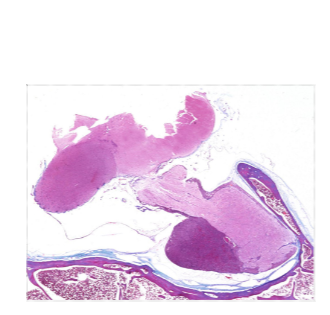

pituitary and hypothalamus